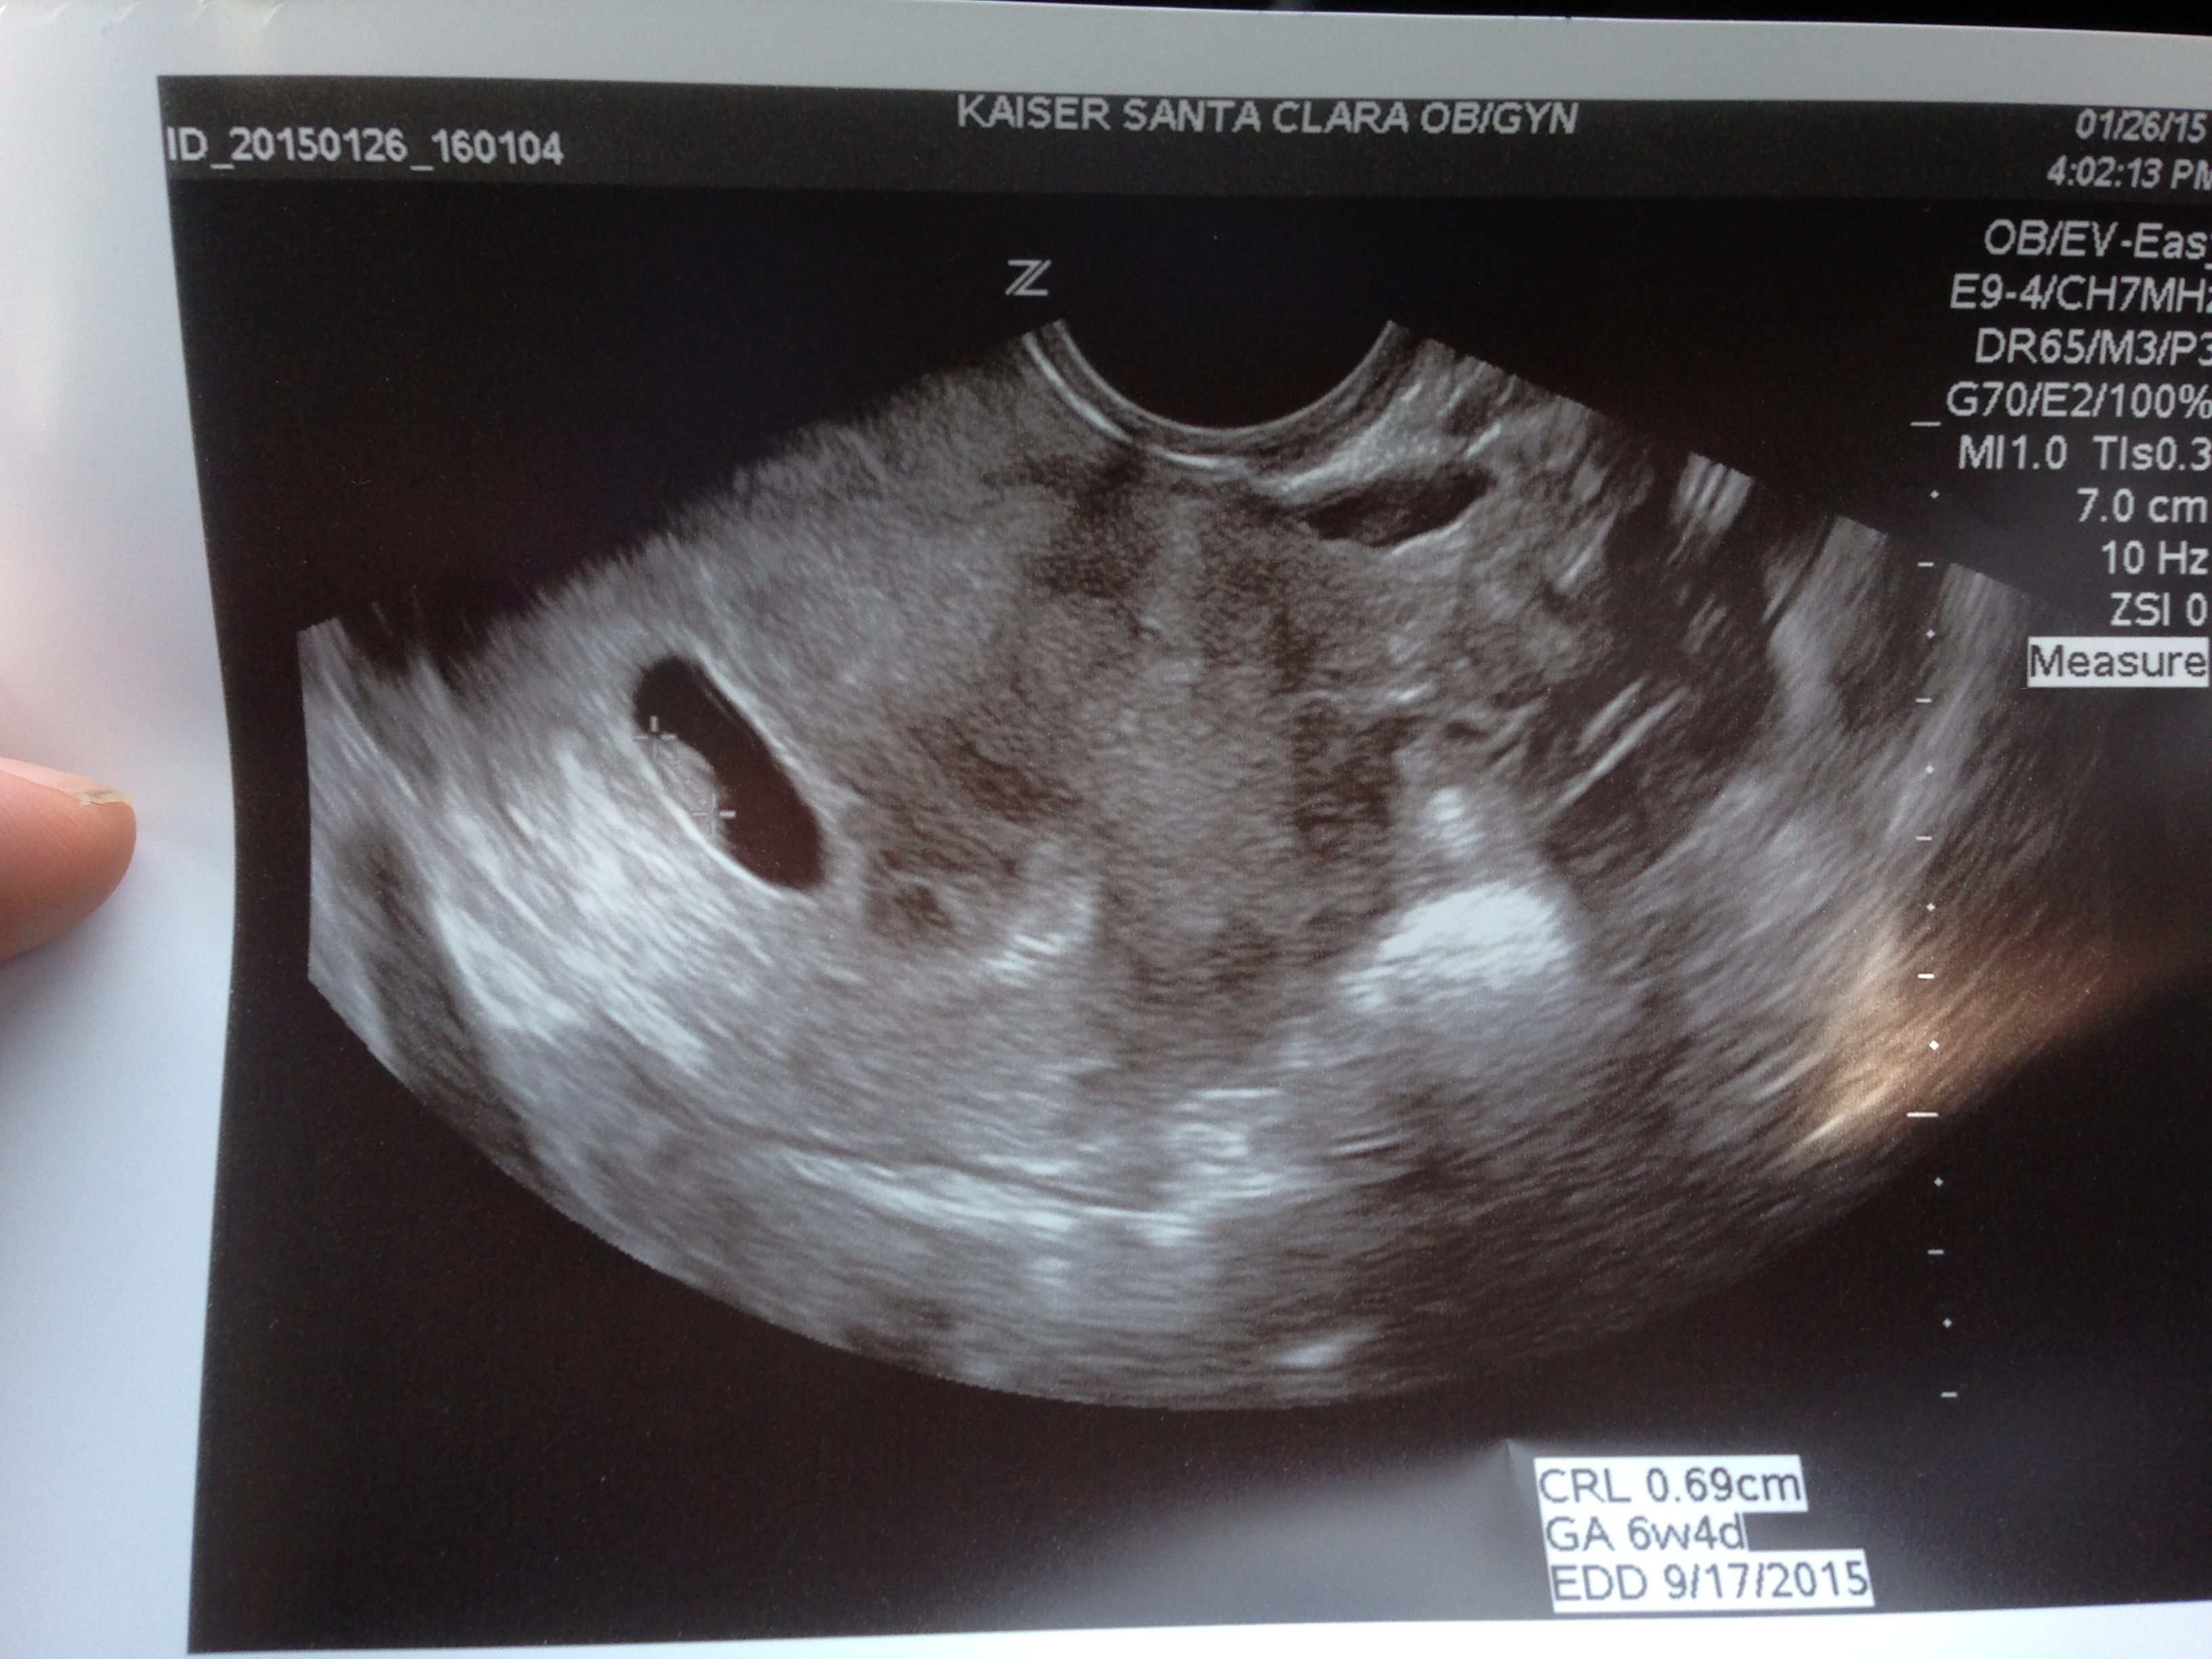

1.26.15

There he is! That little dot is really him. It’s really Keller. And you could really see his little heart beating. Really truly our son. Really very much alive.

But I still got teary eyed when I saw his tiny heart thumping. Butterflies fluttered up inside my throat. “It’s incredible isn’t it?”, my doctor said. Absolutely.